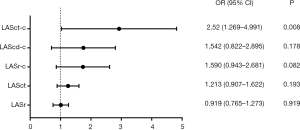

Logistic regression analysis

Logistic regression analysis of patients with AF revealed that LASct-c was independently associated with a high risk of thromboembolism [odds ratio (OR): 2.52, CI: 1.27 to 4.99, P=0.008; Table 3 and Figure 3]. In patients with NVAF, LASct-c was found to be able to distinguish between high and low risk of thromboembolism, and the area under the curve (AUC) was 0.95 (P<0.001; Figure 4). The most approximate Youden index was 0.85, while the corresponding value of LASct-c was –4.5%. At this point, sensitivity and specificity were 0.872 and 0.978, respectively.